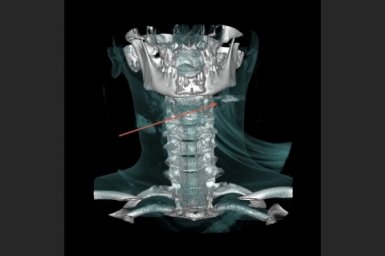

Ранее ИА PrimaMedia сообщало, что девочка, находясь дома, взяла пневматический пистолет отца и при попытке зарядить его случайно выстрелила себе в шею. Пострадавшая была срочно госпитализирована и доставлена во Владивосток, где ей была проведена операция.

Челюстно-лицевые хирурги во Владивостоке извлекли пулю из шеи девочки-подростка

Челюстно-лицевые хирурги во Владивостоке извлекли пулю из шеи девочки-подростка Сложнейшую операцию с ювелирной аккуратностью и точностью проводили хирурги "второй" краевой